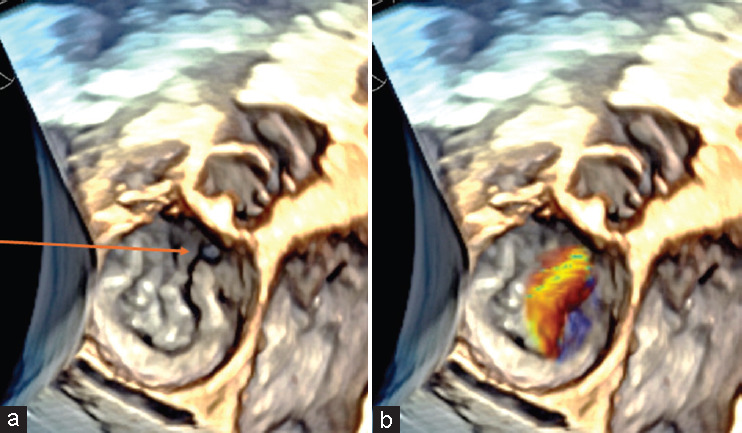

Methods: Recent advancements in the field of miniaturization have led to the development of a new pediatric 3D TEE probe, specifically designed for young children (weight ≥4.5 kg). This probe features a smaller, flexible design and high-spatial and temporal resolution, enabling detailed views of intracardiac structures and real-time imaging crucial for complex diagnosis, planning interventional and surgical procedures. We used this new probe in pediatric cases (weight between 4.5 and 6 kg) with complex congenital heart disease.

Results: In double-outlet right ventricle or in Taussig Bing anomaly the new 3D TEE probe enabled detailed assessment of ventricular septal defect and its relations with tricuspid valve apparatus, and provided details of mitral valve leaflets not detectable by the transthoracic approach, even in small children.